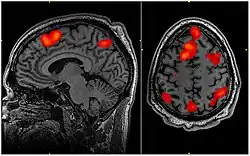

The neuroscientific underpinnings of flow are a developing field with significant potential. With advancements in neuroimaging technologies, as highlighted by Linden (2021), the opportunity to correlate psychological experiences of flow with their physiological counterparts becomes increasingly feasible.[124]